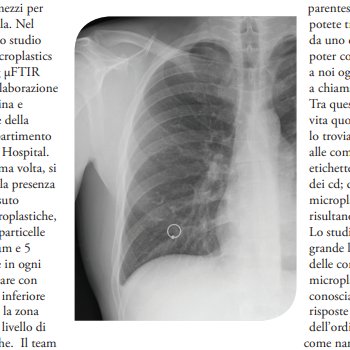

TRACCE DI MICROPLASTICHE NEI POLMONI UMANI

Si parla costantemente di inquinamento causato dalle materie plastiche, per le strade, nelle foreste, nei mari, dalle immense isole di rifiuti galleggianti fino alle più profonde depressioni oceaniche. Oggi ci teniamo a parlare di come abbiamo scoperto la presenza di queste materie plastiche in un luogo di cui molti non sospettano, i polmoni umani, i nostri polmoni.

In questo studio, per la prima volta, si è indagata con accuratezza la presenza di materie plastiche nel tessuto polmonare umano. Le microplastiche, definite nello studio come particelle di plastica comprese tra 1 μm e 5 mm, sono state individuate in ogni regione del tessuto polmonare con una prevalenza per la parte inferiore seguita da quella superiore, la zona mediana presenta un basso livello di deposito delle microplastiche. Il team di ricercatori ha identificato 39 microplastiche in 11 dei 13 campioni di tessuto polmonare, con una media aggiustata di 0,69 ± 0,84 microplastiche per grammo di tessuto. A differenza dello studio di Pauly et al. del 1998 si è notato come le microplastiche siano presenti in tutte le regioni polmonari e non relegate esclusivamente ai grandi spazi aerei.